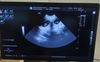

Der heutige Ultraschalltermin hat uns endlich die Gewissheit gebracht, auf die wir in den letzten Wochen so gespannt gewartet haben. Mehrere kleine Fruchthüllen waren gut zu erkennen und auch erste Herzschläge konnten wir sehen – ein Moment, der einen jedes Mal aufs Neue berührt.

Wir freuen uns auf alles, was jetzt kommt und bedanken uns für alle gedrückten Daumen, lieben Nachrichten und guten Gedanken! Anbei noch ein erstes Bild von 2 G-chen.